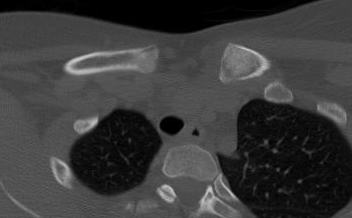

CT scan

Left posterior SCJ dislocation with pre- and post angiogram

Left posterior SCJ dislocation with pre- and post angiogram

Severe left posterior SCJ dislocation with subclavian vein compression